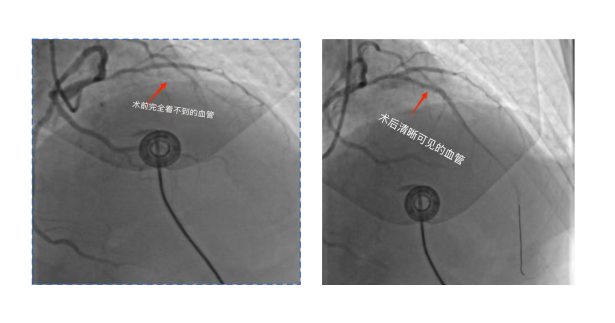

我院胸痛中心立即启动绿色通道,绕行病房,直接将陈叔送入介入导管室行急诊PCI术。尽管手术团队迅速开通血管、成功置入一枚支架,但就在这关键时刻,险情再生!陈叔突然气促加重、咳粉红色泡沫痰,血压下降——这是急性左心衰心源性休克的危重表现,死亡率极高!

介入室内气氛瞬间凝固,但心血管内科团队与介入科团队训练有素、临危不乱。丁明学主任当机立断:“立即启用IABP(主动脉内球囊反搏)支持!” 置管、连接、反搏……一系列操作快、准、稳。随着IABP的规律运行,这颗濒临崩溃的心脏终于获得了宝贵的“喘息之机”,血压稳步回升,生命通道被再次牢牢守住!